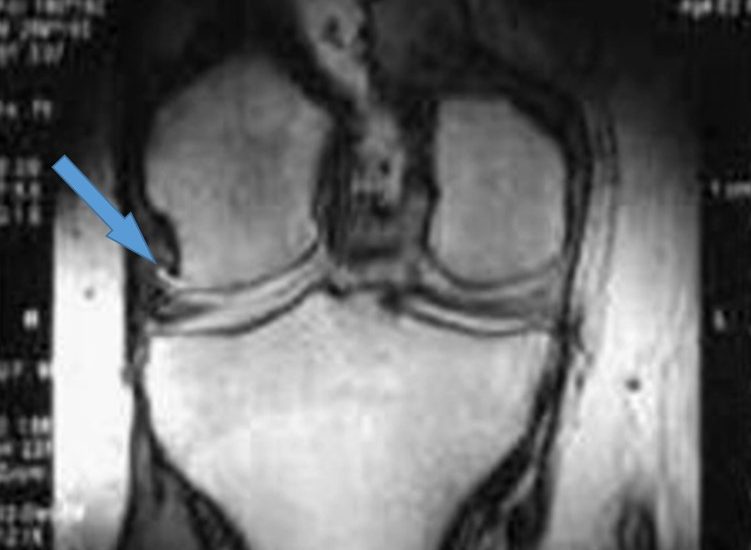

Хвороба Кеніга (розсікаючий остеохондрит колінного суглоба) – досить рідкісне захворювання, при якому розвивається обмежений остеонекроз ділянки субхондральної кістки, внаслідок чого відбувається дегенерація та відділення хрящової тканини в ділянці некрозу з подальшим зміщенням фрагмента